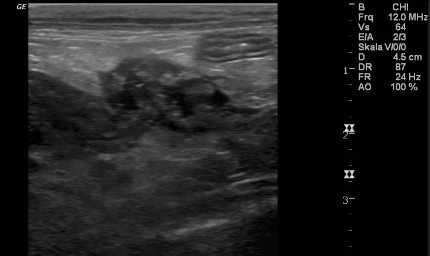

Niere und Harnableitendes System

Akute- und chronische Erkrankungen der Blase- und der Niere werden nicht selten unterschätzt. Einen Funktionsverlust der Nieren kann man im Akutfall nur mit sofortiger intensiver Therapie beheben und den chronischen Funktionsverlust nur Aufhalten jedoch selten noch ausheilen. Harnstoff und Kreatinin sind Funktionsparameter der Niere die erst verändert sind, wenn 80% des Nierengewebes bereits funktionslos geworden sind. Frühere Marker sind der SDMA-Marker und die UPC.

![]() |